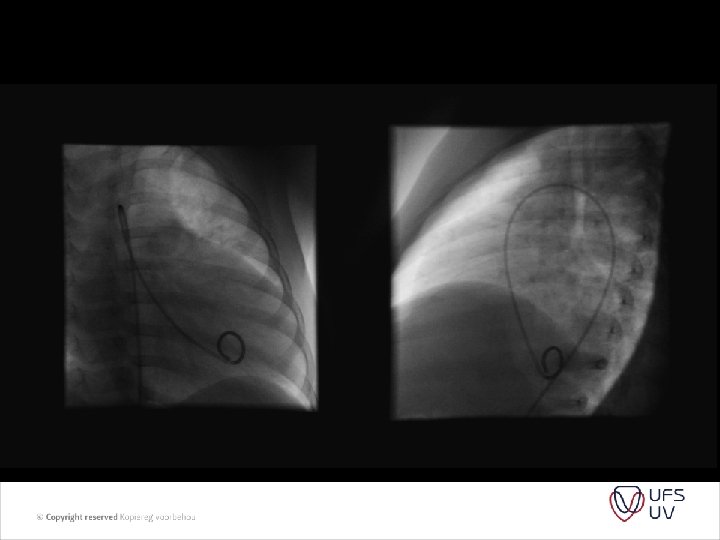

PVR = PAP/ PAflow Substitude PA pressure with TR jet Substitude PA flow by RVOT VTI (velosity time integral) And we get PVR = TR jet velocity/ RVOT VTI x 10

• • Figure 1 Images showing peak tricuspid regurgitant velocity (TRV) and right ventricular outflow time-velocity integral (TVIRVOT) in a patient with normal pulmonary vascular resistance (PVR). (A) TRV is 2. 86 m/s. (B) TVIRVOT is 20. 8 cm. The ratio of TRV/TVIRVOT = 2. 86/20. 8 = 0. 1375. . This patient’s invasive PVR measurement was within 0. 4 WU of the echocardiographic value (PVRCATH = 1. 3 WU). PVRECHO = PVR in WU calculated based on the linear regression equation in which a value for PVR in WU was modeled based on TRV/TVIRVOT. PVRCATH = invasive PVR.

• Figure 2 Images showing TRV and TVIRVOT in a patient with elevated PVR. (A) TRV is 3. 64 m/s. (B) TVIRVOT shows a clear deceleration of pulmonary flow before the pulmonic valve closure click and is calculated at 6. 5 cm. The ratio of TRV/TVIRVOT = 3. 64/6. 5 = 0. 56. . This patient’s invasive PVR measurement is also within 0. 4 WU of the echocardiographic value (PVRCATH = 6. 0 WU). Abbreviations as in Figure 1. • • J Am Coll Cardiol, 2003; 41: 10211027